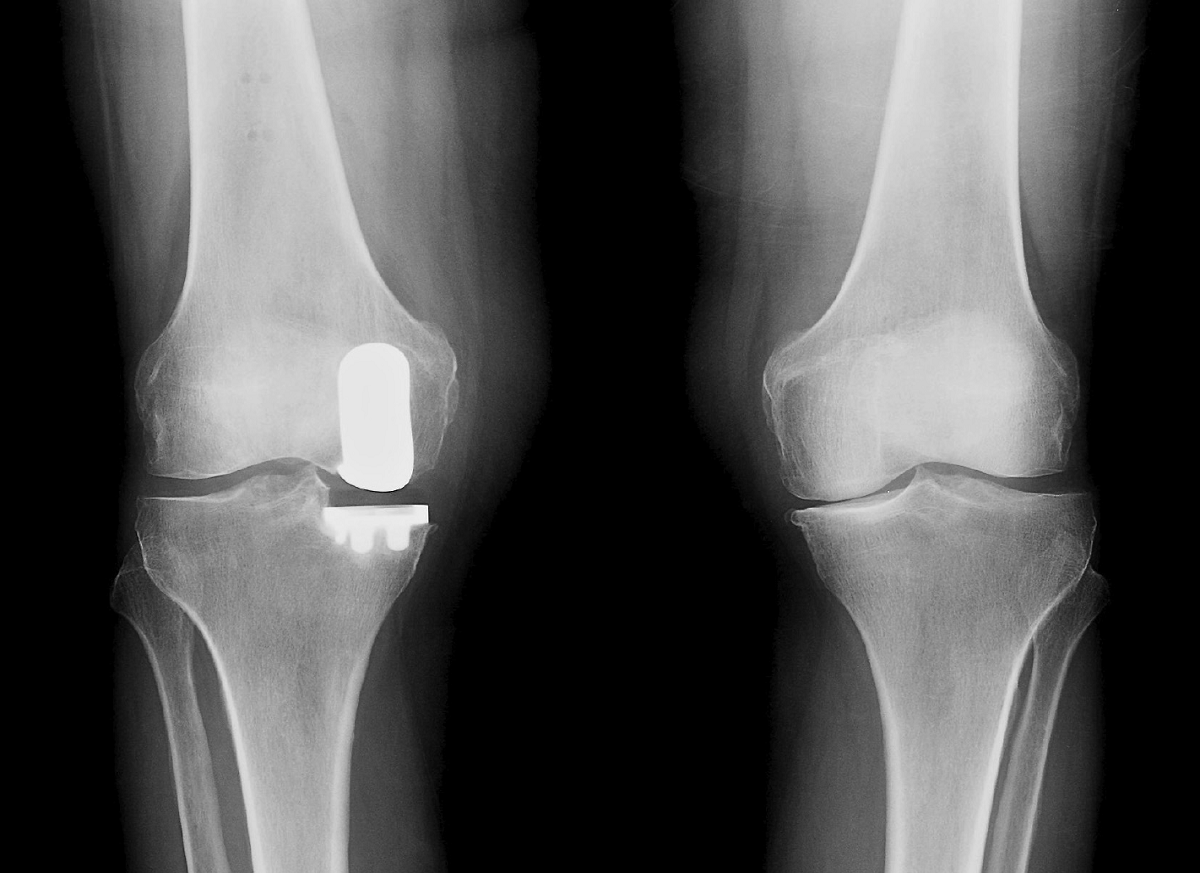

Knee arthroplasty before and after isolated tibial insert exchange to a Knee Replacement Hammering See what happens during knee replacement surgery in this video and learn about the. You may be told to use gentle. Once you’re home, you’ll continue to elevate and ice your knee while taking medication as prescribed or needed. Knee replacement surgery is an effective procedure to relieve pain, correct leg deformity, and help you. People who have to get. Knee Replacement Hammering.